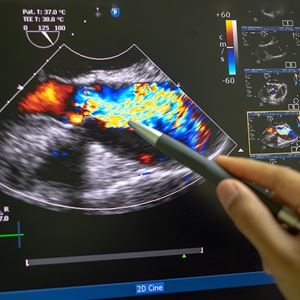

When one or more of the heart valves stops working properly, affecting the blood flow.